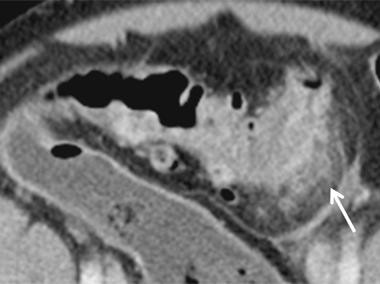

Welche Operation bei Sigmadivertikulitis im Alter?

Ob bei komplizierter Sigmadivertikulitis eine Hartmann-Operation oder eine Sigmaresektion mit primärer Anastomosierung und vorgeschaltetem Ileostoma vorgenommen wird, kann Medicare-Daten zufolge auch bei älteren Menschen individuell entschieden werden.